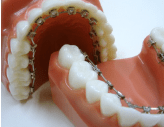

写真④:使用する装置例

使用する装置例

写真⑤:使用する装置例